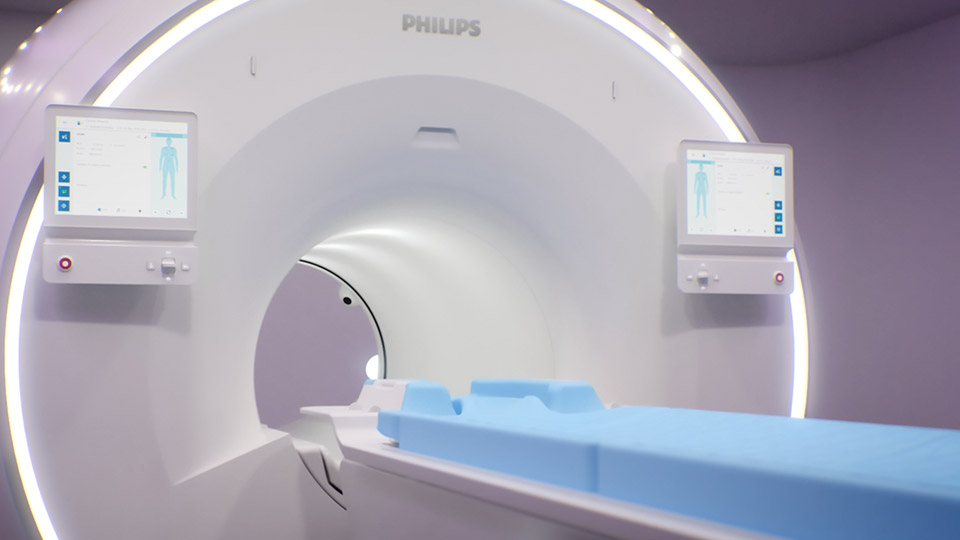

Un avance revolucionario en calidad diagnóstica, y en velocidad

Imágenes 3.0T a su alcance